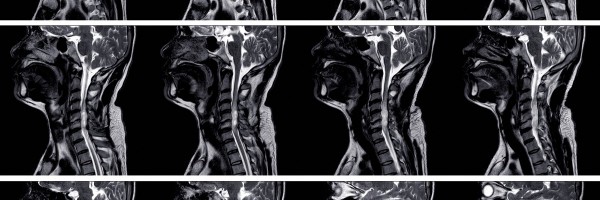

Branchial Cleft Cyst and other anomalies: Causes, Types, Symptoms, Treatment and Surgery

Overview A branchial cleft cyst is a remnant of embryonic development and occurs due to the failure of one or more of the branchial clefts to obliterate. The area of involvement...